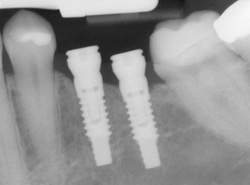

Dental implants are advanced dental solutions designed to replace missing teeth. They consist of a titanium post that is surgically placed into the jawbone, acting as a sturdy foundation for artificial teeth or crowns.

This innovative approach mimics the natural tooth root, providing stability and support for restorations that look, feel, and function like real teeth.

In cases where several teeth are missing, multiple implants can be strategically placed to support bridges or even full arch restorations, offering a comprehensive solution.